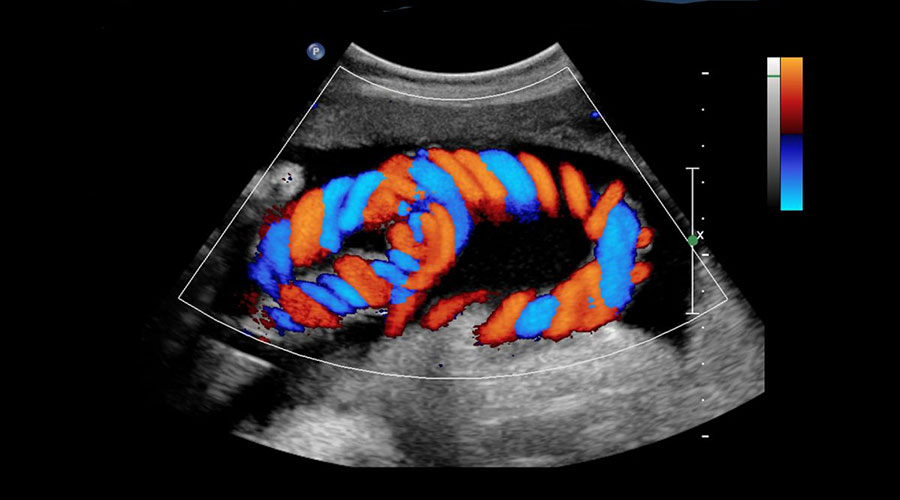

Color Doppler Ultrasonography

Color doppler, one of the ultrasound imaging techniques, is used to detect blood flow in the vessels and to image organs within the body using high-frequency sound waves. First, sound waves are sent through the probe. Likewise, the returning sound waves are collected by the probe and converted into electrical energy. It is also converted into an image by computer. It is used in the examination of many parts of the body. The main areas of use are; It can be summarized as intra-abdominal organs, superficial organs such as thyroid gland, breast, pregnancy follow-up, heart, arteries and veins.